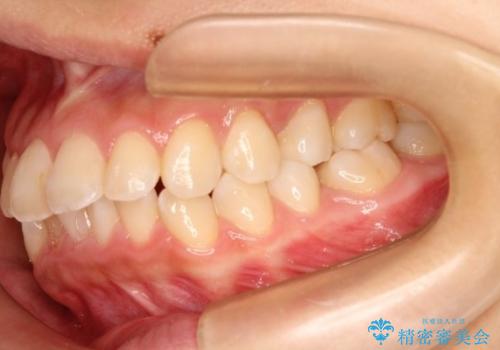

【非抜歯矯正】できる限り前歯を引っ込めたい

- 前歯の凸凹を主訴に来院されました。

非抜歯の範囲でできるだけ前歯を下げることを希望されたため、IPRと臼歯部の遠心移動を行い治療を行いました。当初はインビザラインで治療を行っておりましたが、使用時間を十分に確保できないことで途中からワイヤーを使用しております。